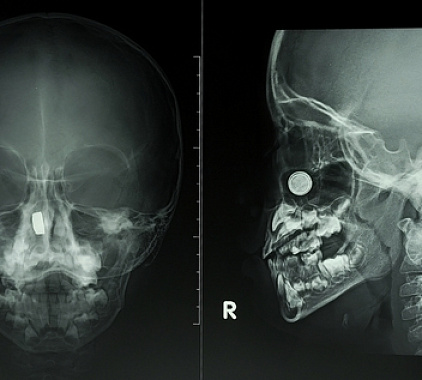

В протоколе диагностического исследования врач описывает состояние околоносовых пазух, голосовых связок, костных структур, лимфоидного кольца. Специалист сравнивает показатели с нормой, выявляет различные изменения. Помимо этого, рентгенолог отражает видимые патологии и их характеристики. В конце пишет заключение и рекомендации.

Рентгенограмма носоглотки поможет выявить переломы костей, доброкачественные новообразования и воспалительные процессы околоносовых пазух, повреждения пазух носа, патологические процессы органа слуха, деформации носовой перегородки, аденоиды и иное разрастание лимфоидной ткани. Диагностика информативна в плане визуализации посторонних предметов, онкологических процессов, мукоцеле, пиоцеле, полипозных разрастаний, инфекционных заболеваний, кист, метастатических очагов.

Что показывает рентген носоглотки в боковой проекции?

Процедура отличается высокой информативностью и дает возможность изучить текущее состояние носоглотки. В большинстве случаев данная методика осуществляется в боковой проекции. На получаемых снимках хорошо визуализируется язык, свод носоглотки, вход в гортань. По изменению изучаемых структур доктор затем выявляет возникшие проблемы и их особенности.